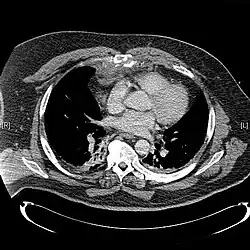

X-rays of the chest are taken in people with chest trauma and symptoms of sternal fractures, and these may be followed by CT scanning.[13] Since X-rays taken from the front may miss the injury, they are taken from the side as well.[14]